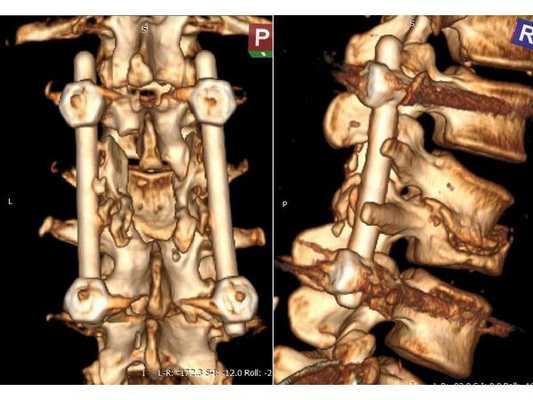

КТ пояснично-крестцового отдела позвоночника показала состояние после перенесённого спондилодисцита L2-L3 (воспалительного заболевания инфекционного характера) с разрушением тела L3 позвонка и кифотической деформацией (искривлением позвоночника) на данном уровне.

Состояние после перенесённого спондилодисцита L2, L3 позвонков с формированием абсолютного стеноза (критического сужения просвета в позвоночном столбе) на уровне L2-L3 и развитием нижнего парапареза

Пациентке проведена операция: транспедикулярная фиксация позвоночника L1-L4 и ламинэктомия L2 (удаление дужки позвонка с целью декомпрессии). Ход операции: • При положении пациентки лёжа на животе в проекции остистых отростков L1-L4 произведён прямой вертикальный разрез мягких тканей размером 10 см. • Надкостницы поперечных отростков и дугоотросчатых суставов отделены от костей. Кровотечение остановлено при помощи электрокоагуляции по ходу доступа. • Под контролем рентгена выявлены ножки L1 и L4 позвонков и сформированы каналы в тела самих позвонков, через которые в их ножки введены моноаксиальные педикулярные винты. • Проведена ламинэктомия позвонка L2. При ревизии твёрдой мозговой оболочки, окружающей спинно-мозговые корешки, на уровне L2-L3 позвонков обнаружены выраженные изменения рубцово-спаечного характера. • Рана промыта при помощи физраствора и раствора перекиси водорода. Поверх твёрдой мозговой оболочки уложена гемостатическая губка. Установлены две продольные штанги, закручены стопорные гайки. • В конце на рану наложен послойный шов нитью Викрил и асептическая повязка.

После операции в неврологическом статусе наблюдается положительная динамика: умеренный парапарез в нижних конечностях почти полностью регрессировал, жалобы на "онемения в ногах" также исчезли. На контрольной КТ видно состояние после успешной декомпрессии на уровне L2-L3 и установки транспедикулярной фиксирующей системы на уровне L1-L4.